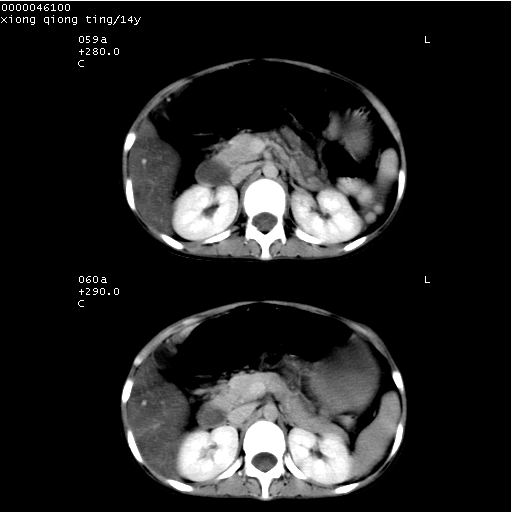

中下腹及盆腔ct轴位平扫+增强扫描(层厚10mm,螺距1.0,重建间隔10mm),图像如下:

(注:患儿检查当日上午9时口服胃肠道对比剂,下午3时许行ct扫描检查,未行对比剂直肠保留灌肠,检查当日患儿腹泻)

中下腹及盆腔ct轴位扫描(ps+ce)提示:腹部肠管明显充气扩张,并见数个不同宽度之气液平面;疑不全性肠梗阻或肠郁张。临床会诊考虑为患儿腹泻,肠郁张所致;后来未经特殊处理,患儿大便恢复正常,亦无腹胀。